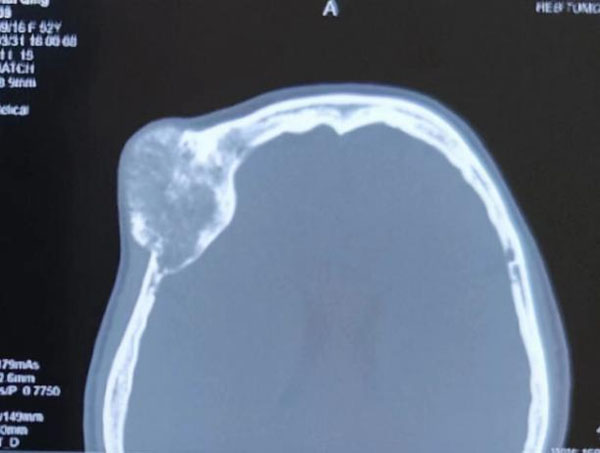

患者主因右眼视物不清伴眼球突出3年,以右眼眶内占位收入我院眼科。眼科郝玉华教授在检查中发现,患者右眼视力极低,右眼上睑下垂,眼球突出且运动明显受限。眼眶CT提示眶内巨大占位,几乎占据球后整个眶间隙。同侧额部颅骨骨质亦显示巨大肿瘤,约7*7 cm大小。患者已经有上睑下垂和视力明显下降的症状,表明肿物已经对眶上裂神经和视神经有一定压迫。